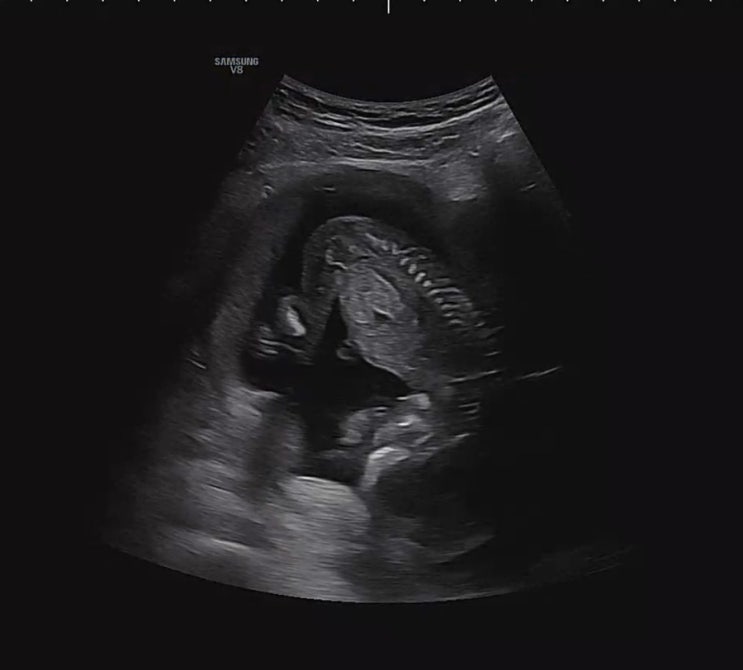

임신일기 :: 12주-16주 1차 기형아검사, 2차 기형아검사, 성별확인

임신 12주 설 연휴가 끝난 2월12일 연휴동안 코로나에 걸리는 바람에 병원 가는날이 더 기다려 졌어요 #임...